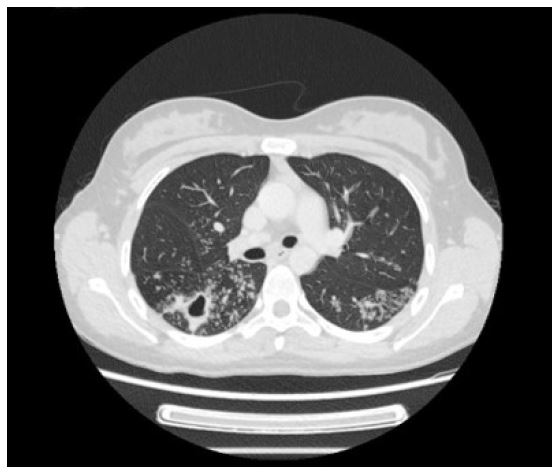

A direct laryngoscopy with biopsy was performed in the following month, and biopsies were taken from the left false vocal cord, anterior commissure, left aryepiglottic fold and the laryngeal aspect of the epiglottis. In several of these biopsies necrotizing granulomatous inflammation with suppuration was identified, characterized by aggregates of epithelioid histiocytes and occasional Langhans type multinucleated giant cells surrounding geographic areas of necrosis (Figure 1). Neutrophilic infiltration of the underlying cartilage was seen in places. No acid-fast bacilli were identified with a Ziehl-Neelsen stain. PAS and Grocott stains were negative for fungal hyphae. Shavings from these biopsies were also submitted for PCR, which detected Mycobacterium tuberculosis.

Figure 1: Histological section from a biopsy of the laryngeal aspect of the epiglottis showing necrotising granulomatous inflammation with suppuration.